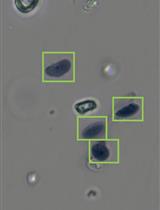

BE2C cells (American Type Culture Collection, CRL-2268)